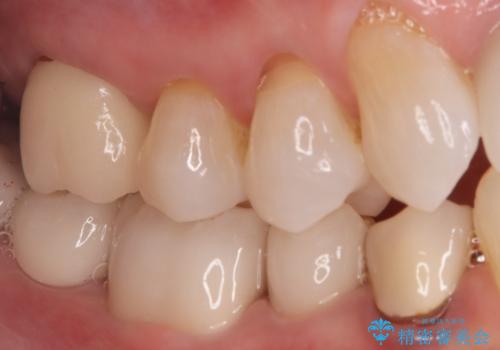

オールセラミッククラウンによる修復: 根管内が清潔に封鎖されたことを確認した後、土台を立てて歯の形を整えました。最終的な被せ物には、金属を一切使用しないオールセラミッククラウンを選択。天然歯のような透明感を再現し、高い適合性によって再び虫歯になるリスクを抑えています。

今回の治療により、詰め物が取れた根本的な原因が解消され、見た目も美しく、長持ちする奥歯を再建することができました。